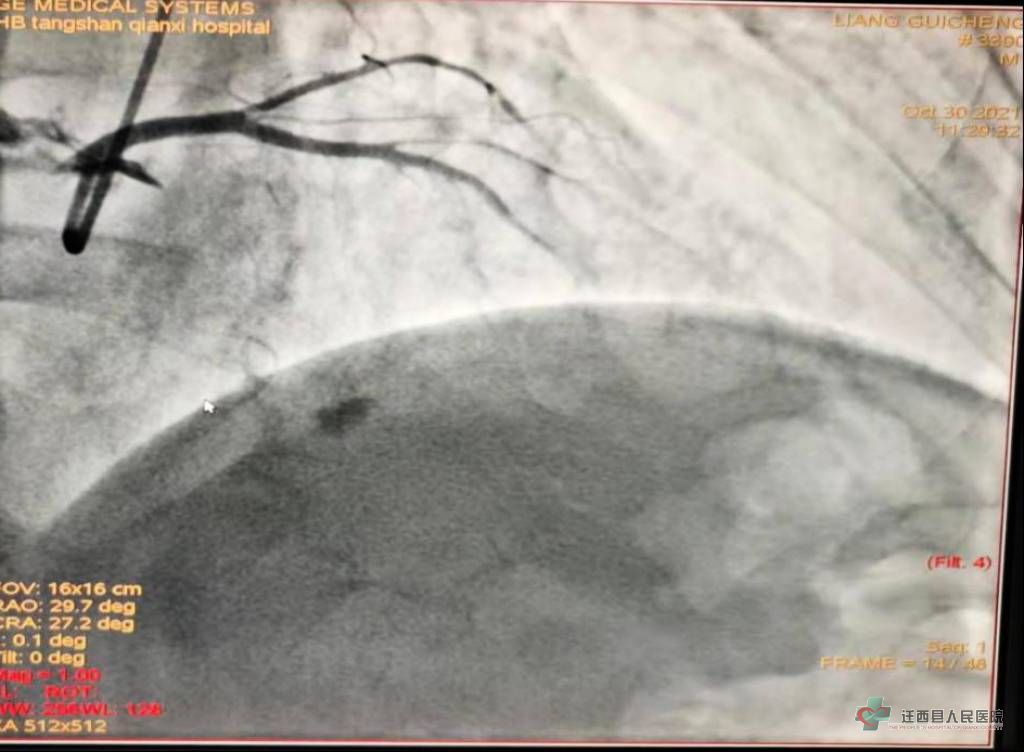

冠脉造影:回旋支开口狭窄60-70%,疑似血栓影。这样的影像不植入支架能放心吗?如果有斑块破裂会不会进展为心梗啊!

术中经IVUS证实:患者回旋支开口见动脉粥样硬化斑块及脂质斑块,未见破裂斑块、血栓及血管夹层,斑块负荷最重达管腔面积仅为32%,考虑冠脉痉挛所致,无需植入支架,给予药物治疗即可。